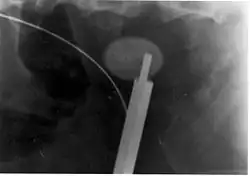

Ureteroscopic surgery

Ureteroscopy has become increasingly popular as flexible and rigid fiberoptic ureteroscopes have become smaller. One ureteroscopic technique involves the placement of a ureteral stent (a small tube extending from the bladder, up the ureter and into the kidney) to provide immediate relief of an obstructed kidney. Stent placement can be useful for saving a kidney at risk for postrenal acute kidney failure due to the increased hydrostatic pressure, swelling and infection (pyelonephritis and pyonephrosis) caused by an obstructing stone. Ureteral stents vary in length from 24 to 30 cm (9.4 to 11.8 in) and most have a shape commonly referred to as a "double-J" or "double pigtail", because of the curl at both ends. They are designed to allow urine to flow past an obstruction in the ureter. They may be retained in the ureter for days to weeks as infections resolve and as stones are dissolved or fragmented by ESWL or by some other treatment. The stents dilate the ureters, which can facilitate instrumentation, and they also provide a clear landmark to aid in the visualization of the ureters and any associated stones on radiographic examinations. The presence of indwelling ureteral stents may cause minimal to moderate discomfort, frequency or urgency incontinence, and infection, which in general resolves on removal. Most ureteral stents can be removed cystoscopically during an office visit under topical anesthesia after resolution of urolithiasis.[116] Research is currently uncertain if placing a temporary stent during ureteroscopy leads to different outcomes than not placing a stent in terms of number of hospital visits for post operative problems, short or long term pain, need for narcotic pain medication, risk of UTI, need for a repeat procedure or narrowing of the ureter from scarring.[117]

More definitive ureteroscopic techniques for stone extraction (rather than simply bypassing the obstruction) include basket extraction and ultrasound ureterolithotripsy. Laser lithotripsy is another technique, which involves the use of a holmium:yttrium aluminium garnet (Ho:YAG) laser to fragment stones in the bladder, ureters, and kidneys.[118]